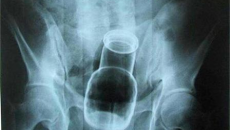

Вадят флакон за бръснене от мъж

Търновски хирурзи извадиха флакон с пяна за бръснене от ректума на 35-годишенмъж.Пациентът, който е баща на 2 деца, обяснил, че изпуснал пяната, докато себръснел в банята. Навел се да вземе флакона, но се подхлъзнал и се нанизал нанего. Търновецът оп...